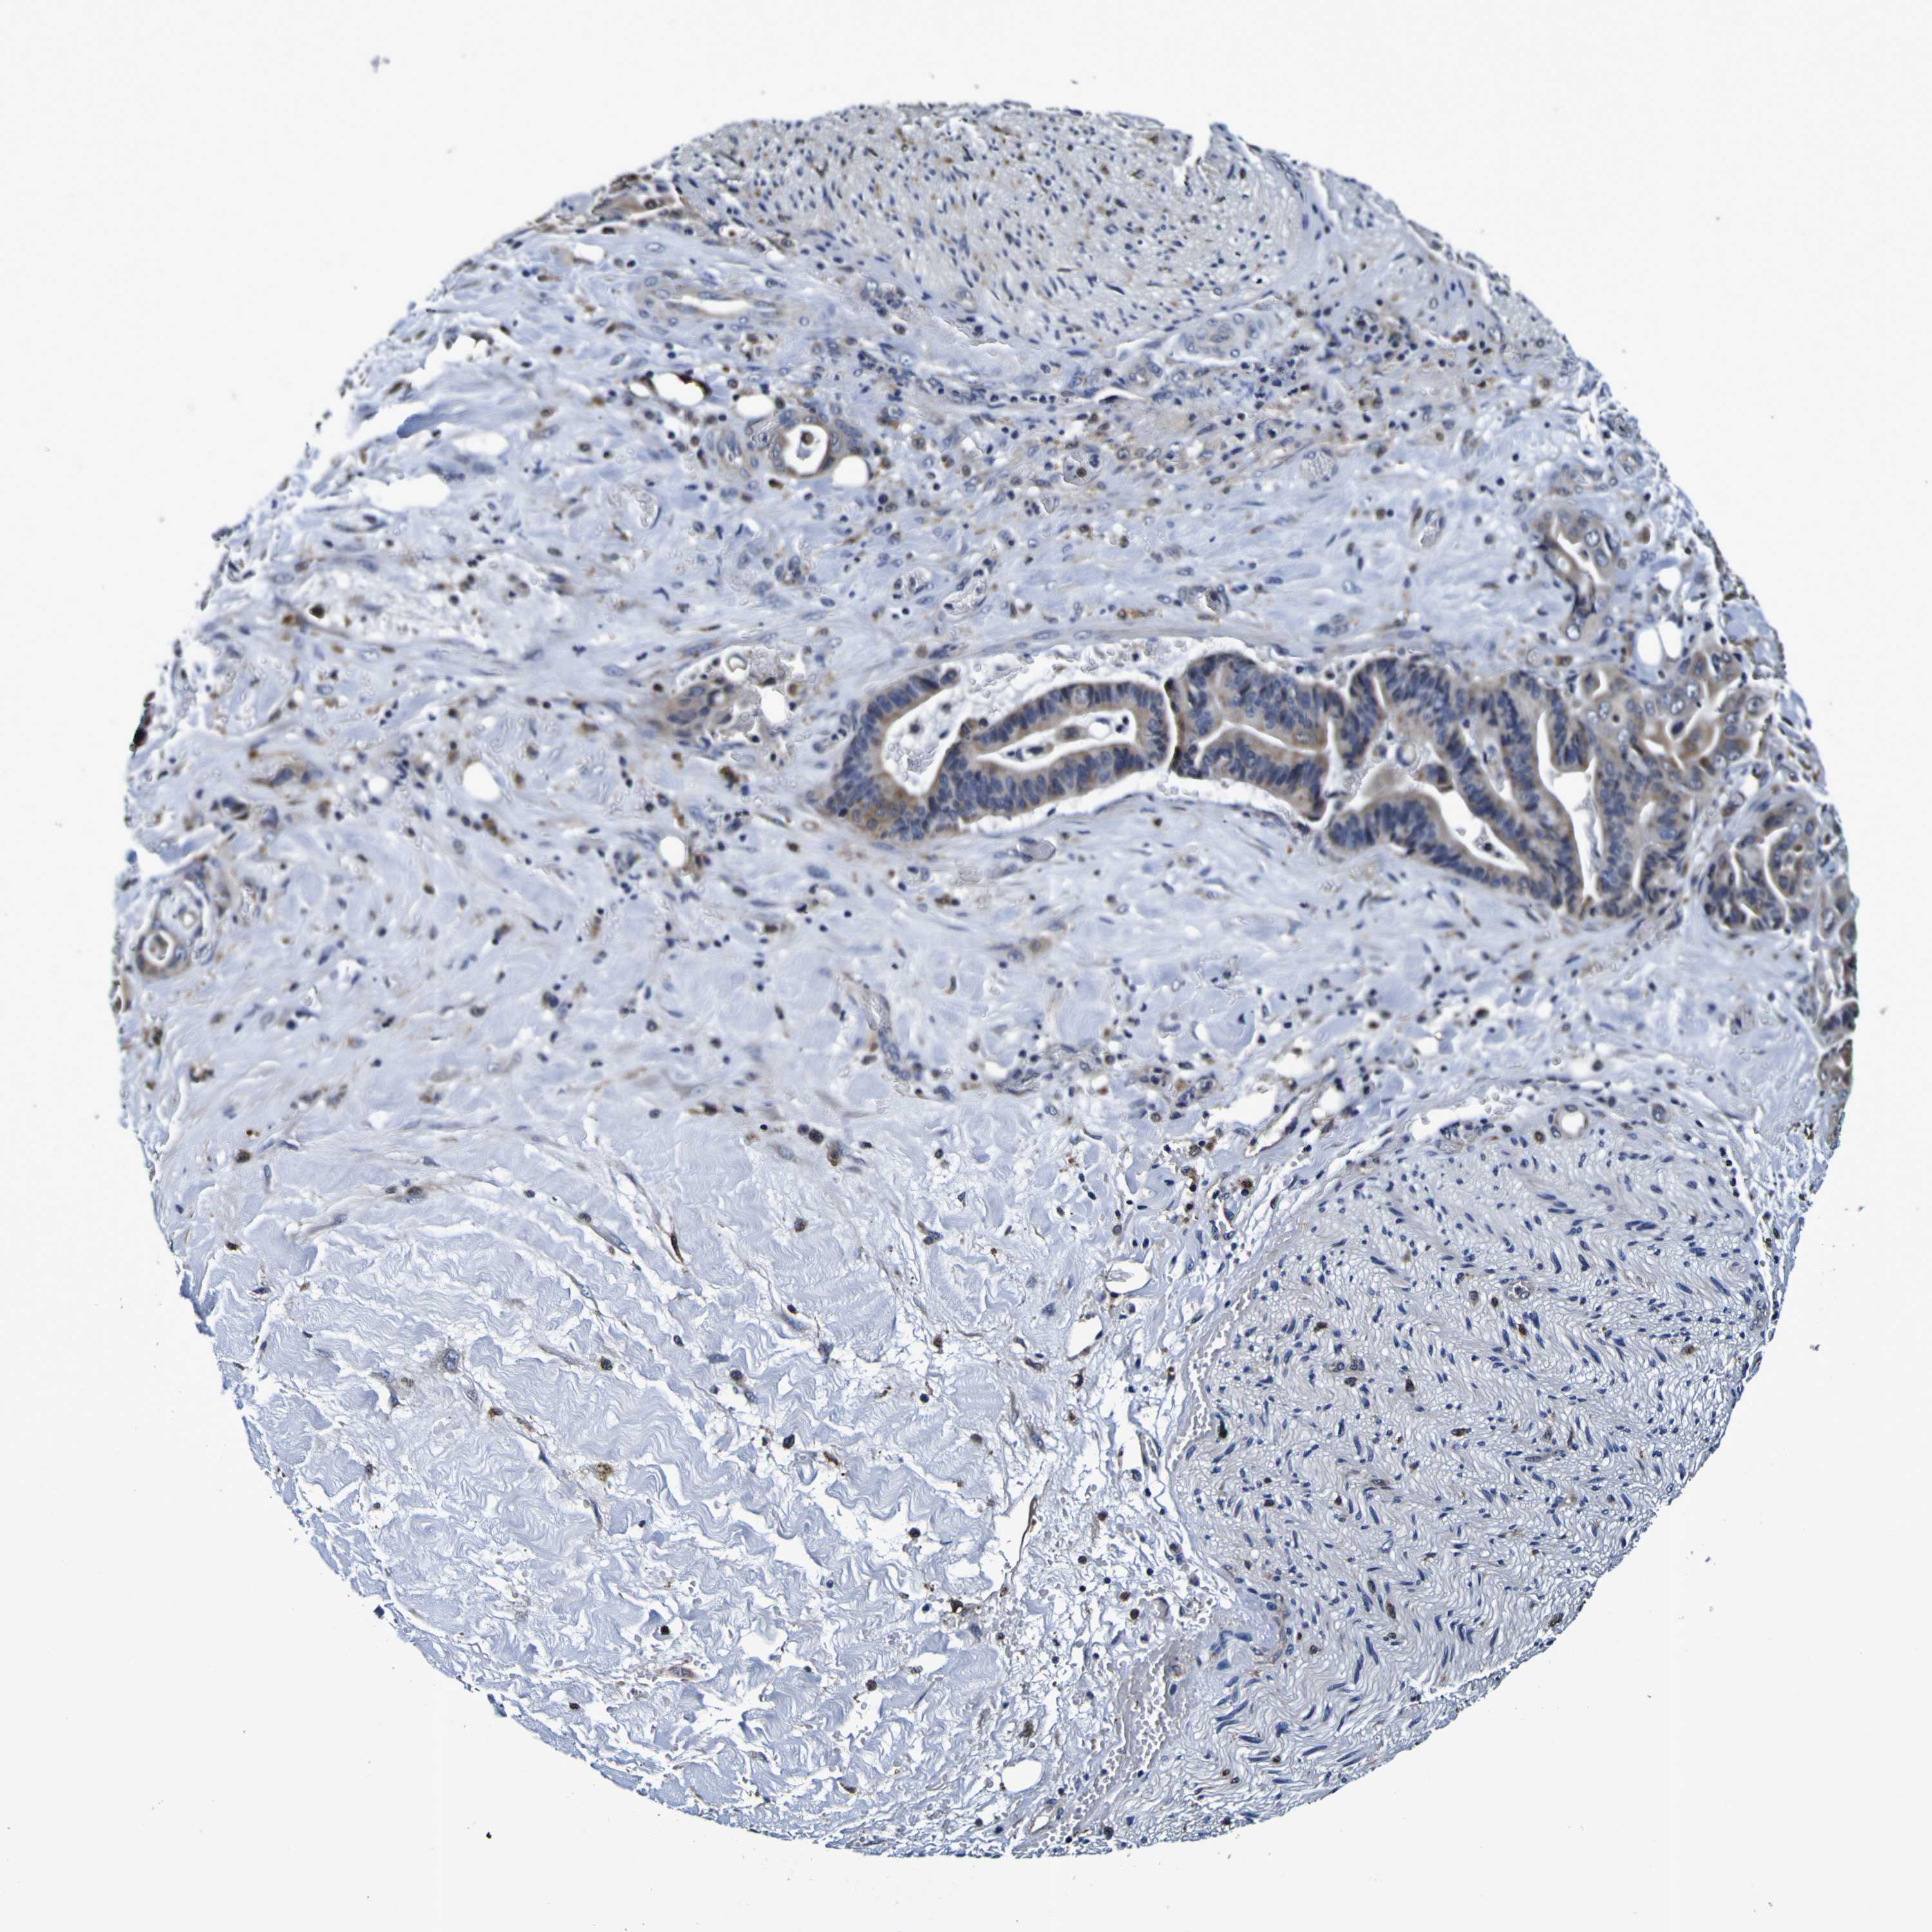

LIVER CANCER - Protein expressioni

A mouse-over function shows sample information and annotation data. Click on an image to view it in a full screen mode. Samples can be filtered based on level of antibody staining by selecting one or several of the following categories: high, medium, low and not detected. The assay and annotation is described here.

Note that samples used for immunohistochemistry by the Human Protein Atlas do not correspond to samples in the TCGA dataset.

Antibody stainingi

Antibody staining in the annotated cell types in the current human tissue is reported as not detected, low, medium, or high, based on conventional immunohistochemistry profiling in selected tissues. This score is based on the combination of the staining intensity and fraction of stained cells.

Each image is clickable and will lead to virtual microscopy that enables deeper exploration of all samples and also displays staining intensity scores, fraction scores and subcellular localization as well as patient and tissue information for each sample.

Antibody HPA044758

Antibody CAB011582

Staining

High

Medium

Low

Not detected

Intensity

Strong

Moderate

Weak

Negative

Quantity

>75%

75%-25%

<25%

None

Location

Nuclear

Cytoplasmic/membranous

Cytoplasmic/membranous,nuclear

Cholangiocarcinoma

Carcinoma, Hepatocellular, NOS